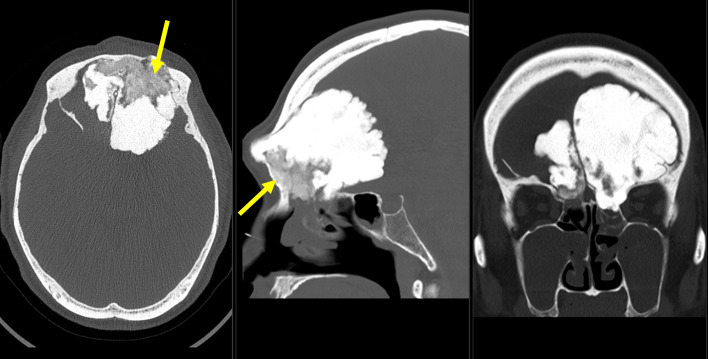

Fig. 1.

Axial, sagittal, and coronal view of head CT. A lobulated mass, 8.4 cm in length is seen just below the frontal bone. The tumor extends into the olfactory fossa and ethmoid sinus. The bilateral orbital walls are deformed, thinned, and partially missing. Most of the mass has a density equivalent to that of bone cortex, while the basal areas show a ground-glass density (arrows).